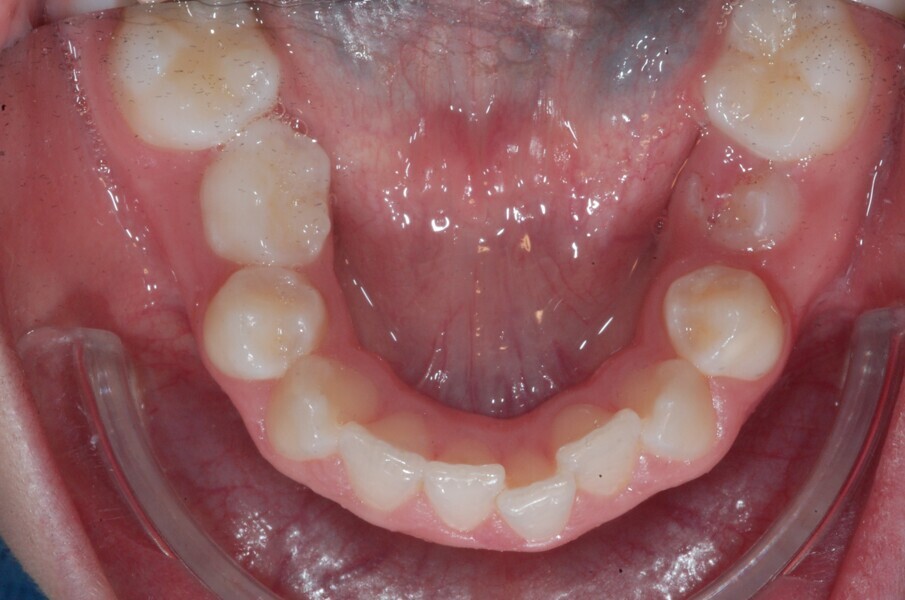

A 14-year-old female patient presented with the chief complaint of midline deviation and dental crowding in both arches. Facial analysis showed a hypodivergent growth pattern, a normal nasolabial angle, a harmonious profile and proper chin projection. Clinical examination revealed a Class III skeletal relationship (ANB = 0°) and Class I molar relationship. The maxillary right canine was absent, and this had led to space loss and mesial drift of posterior teeth on the right side, resulting in a slight Class II molar relationship. The maxillary left canine had erupted in a high position. The mandibular arch displayed crowding despite the agenesis of the right second premolar and the persistence of the primary molar (Figs. 3–11). The radiograph showed the probably premature loss of the maxillary right primary canine and consequently impacted maxillary right permanent canine, and the agenesis of the mandibular right second premolar and the mandibular right third molar (Fig. 12).

Fig. 3